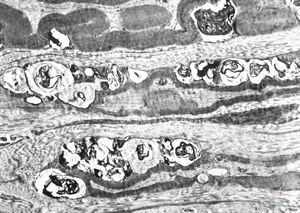

F,25y. | metachromatic leukodystrophy - n. suralis

F,8y. | metachromatic leukodystrophy - n. suralis

F,25y. | metachromatic leukodystrophy - n.suralis